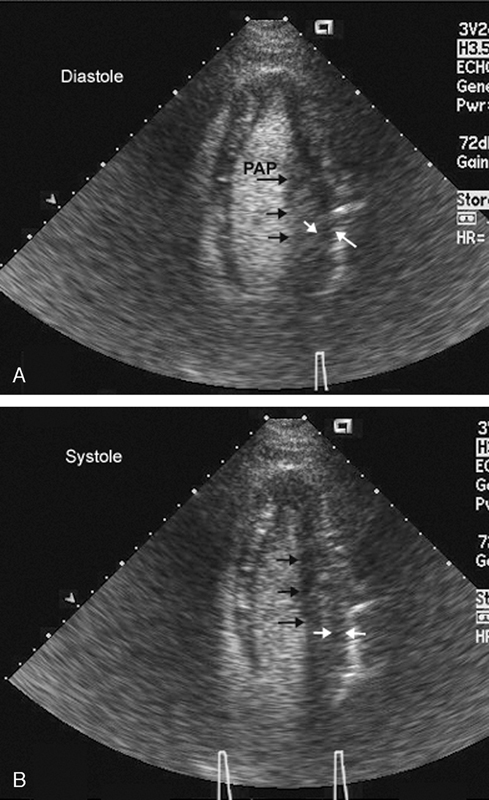

فحوصات تشخيصية لبعض امراض القلب والشرايين التاجية